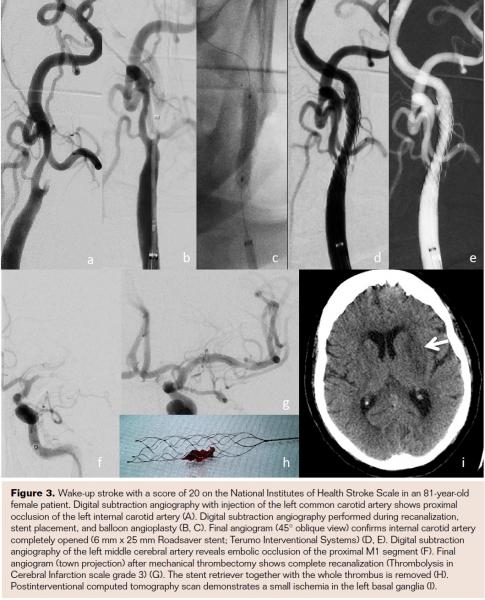

In addition to these first clinical data and experience with the Roadsaver stent, it is necessary to clarify that a certain learning curve for safe and accurate stent placement is warranted. This is because experience is needed to predict the stent length. It is highly recommended to start with larger diameters or longer stent lengths in order to achieve good lesion covering. In Figures 1-3 the Roadsaver stent is shown in 3 different anatomical locations.

The Roadsaver stent (Terumo Interventional Systems) currently is the only FDA-approved, CE-marked, commercially available double-layer micromesh stent. This self-tapering stent is composed of two nitinol (nickel titanium) interwoven mesh layers, creating a flexible scaffold. The inner mesh has an extremely small cell size (0.381 mm2), which is designed to prevent release of emboli. The internal fine meshwork should prevent plaque prolapse.17 A number of micromesh cells fit into one macromesh cell, acting like a metallic covered stent.

The device is compatible with a 5 Fr sheath or 6 Fr guiding catheter. Up to the point of 50% deployment, the push-and-pull stent delivery system is full resheathable and repositionable. The low profile (5 Fr) enhances the crossability for primary stenting. The double-layer micromesh scaffold should enable sustained embolic protection by tight plaque coverage. The feasibility, efficacy, and safety of performing carotid angioplasty and stenting with the Roadsaver stent has been demonstrated in two studies.15,16 Kedev et al used transradial slender 5 Fr techniques to implant the Roadsaver stent in the left and right carotid arteries with promising results.16

Patient enrollment for the prospective, multicenter CLEAR-ROAD trial (Physician-Initiated Carotid TriaL Investigating the Efficacy of Endovascular Treatment of Carotid ARterial Disease with the multilayer ROADsaver stent) closed in February 2016. The primary endpoint, major adverse events (MAEs) at 30 days, was defined as the cumulative incidence of any periprocedural (≤30 days post procedure) death, stroke, or myocardial infarction (MI). Of all patients, 31% were symptomatic, and in 58% of the patients embolic protection devices were used. Technical success was achieved in all cases. The 30-day MAE rate was 2.1% (one patient experienced MI followed by death; another patient experienced a stroke within the first 30 days after the procedure), making the Roadsaver stent safe and effective for endovascular treatment of subjects at high risk for carotid endarterectomy.17